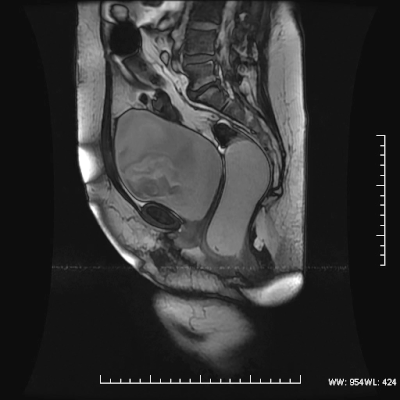

뭐 각설하고 이 영상은 MR defecography라는 검사 기법으로 바로 똥싸는 것을 동영상으로 보여 주는 겁니다. 이걸 왜 하냐고요? 이건 아래 intercourse영상과는 달리 실제적으로 사용되는 검사입니다. 출산후 골반근육이 약해져서 대변을 잘 못보거나 변실금, 방광이나 자궁이 힘줄때 탈출하는 그런 증상의 검사를 위해서 하는 거죠.. 항문에 조영제+감자 갈아넣은거 같은거를 집어 놓고.. 검사 중에 배변을 시킵니다. 그걸 찍는거죠. 과거에는 이걸 x ray를 써서 투시검사로 했었습니다. 한번하면 향기로운 냄새가 검사실에 가득차는.. 물론 환자도 고역입니다. 옆에 누가 서있기만 해도 소변도 잘 안나오는데 여러명이 똥싸는걸 지켜보고 있는데 잘 나오겠습니까.. 게다가 환자들은 거의 대부분 출산이후 골반벽이 약해진 여자분들입니다. 환자가 변을 못봐서 실패도 많이 했던 기억이 있습니다. 그나마 이 X-ray 검사는 양변기 같은거 위에 걸터앉고 시행했습니다만.. 이 MRI는 환자가 누운채로 싸야 합니다. (앉아서 찍는 기계도 있긴 하지만 이 용도로는 거의 안씁니다). 이걸 저희 대장외과 선생님께 보여주니 당장 하자고 하지만.. 찍는거는 어렵지 않지만 방 세팅이 힘들어서.. 게다가 이 다음에 환자 들어가면 컴플레인 작살이겠죠. 그래서 차일피일 미루고 있습니다. (아마 영원히 안할 것 같습니다.)

사진을 보는 법은 앞의 큰 동그라미가 방광이고 뒤가 직장-항문입니다. 직장에 차 있는 변이 어떻게 나오는지를 감상하시면 되겠습니다. 이 영상은 환자는 아니고 정상 지원자입니다.